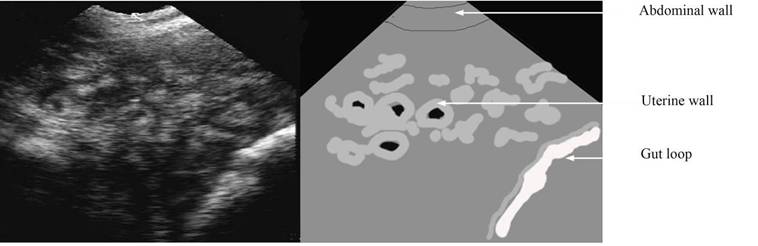

Pseudopregnancy – around 35 days

Note while there appears to be black holes there are no embryos

Sometime the uterine lumen may be filled with a “grains”

repro draw pseudopreg label.jpg